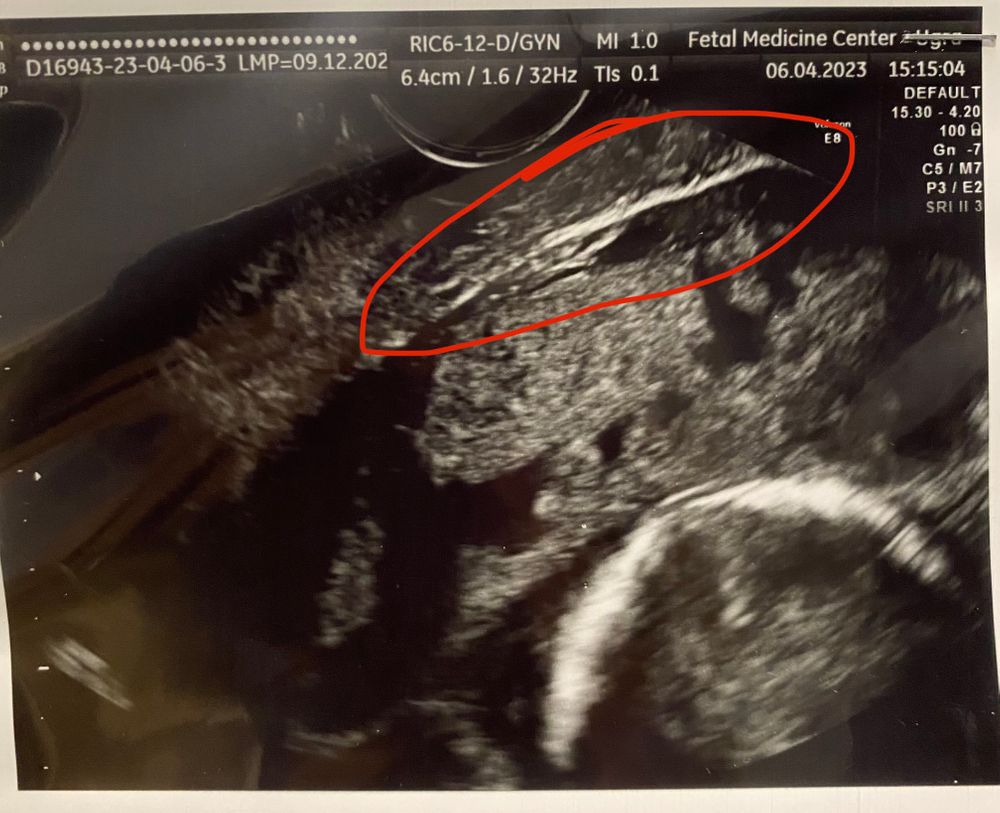

Девочки привет. Сегодня срок 16,6, плацента так и не поднялась, и уже поднимется врядли, сказали. Плюс к этому возможно врастание в рубец. По узи уже вроде как частично вросла.

На фото рубец и плацента.